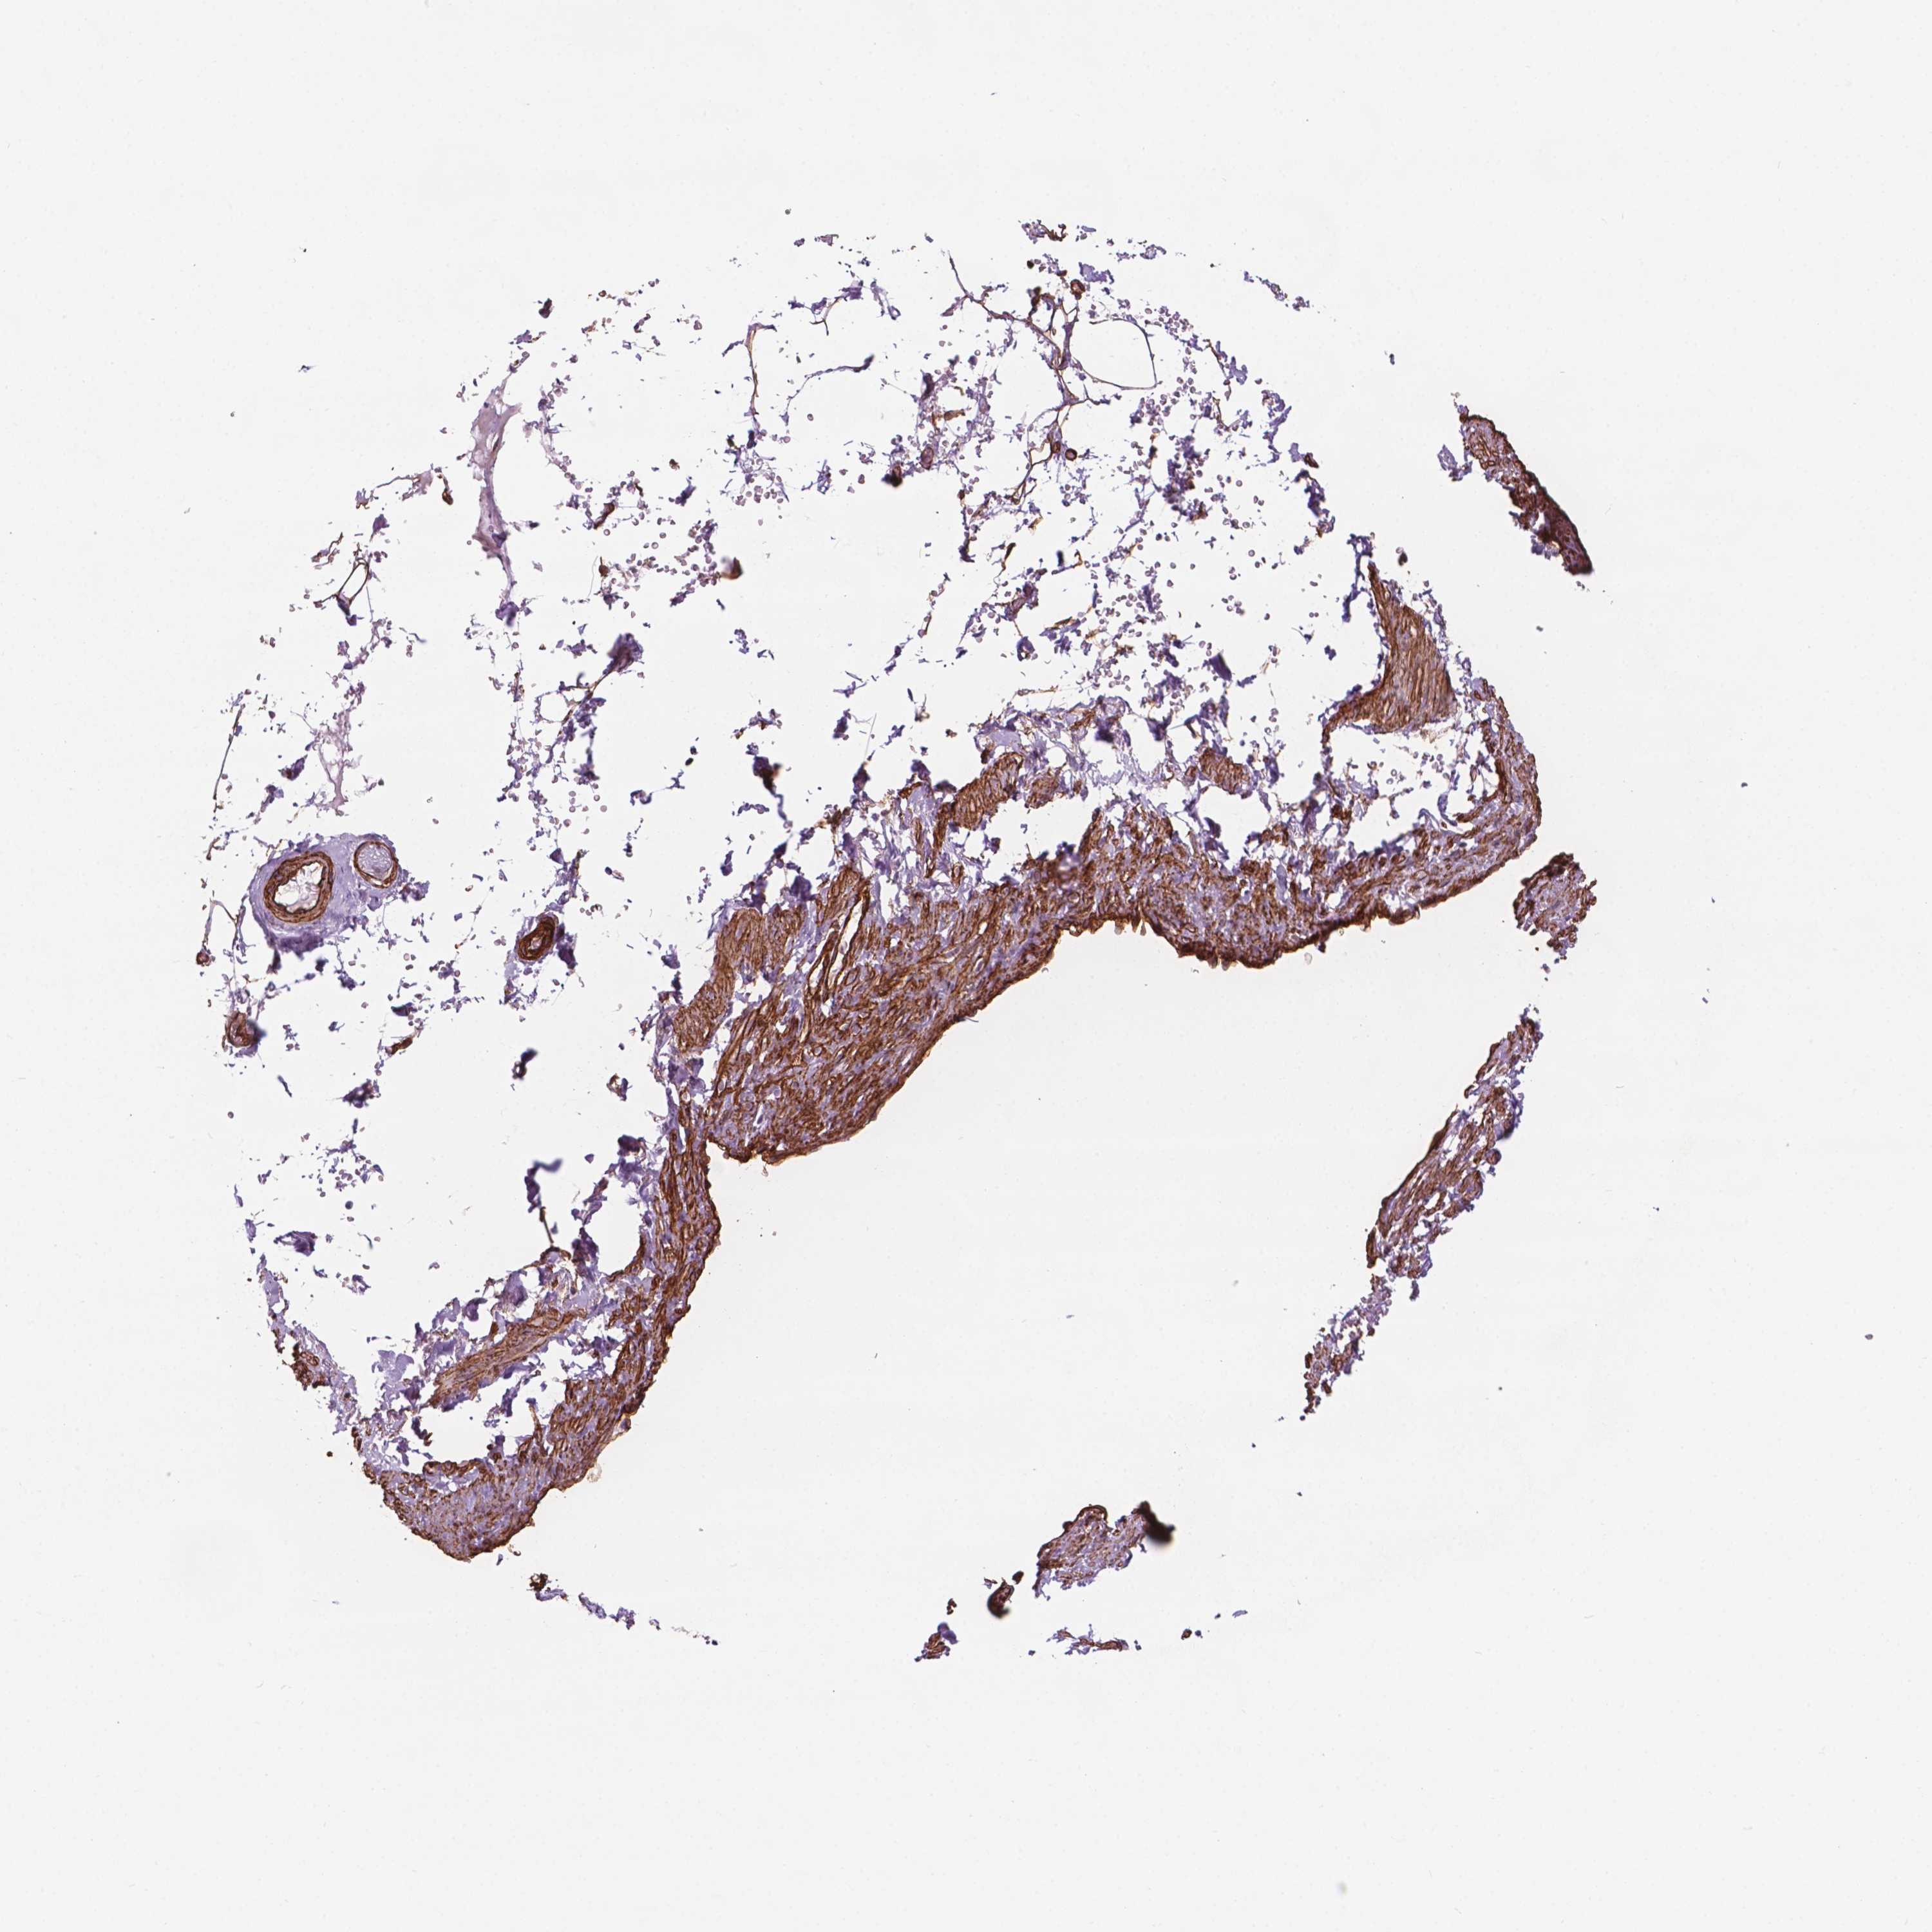

EGFL8